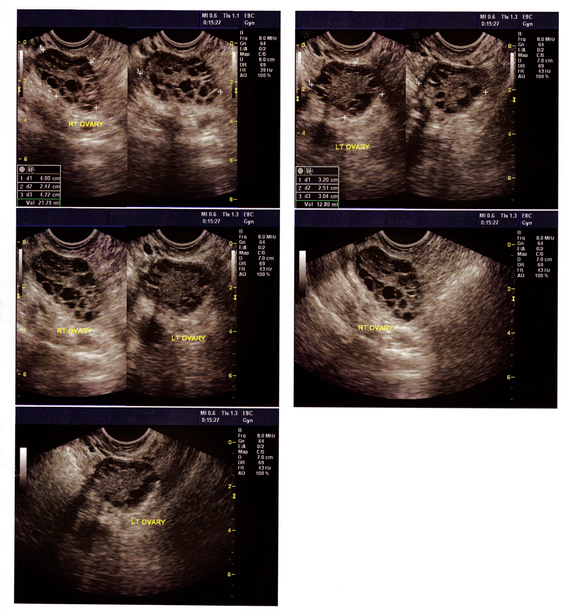

Read MoreDuring this time, your ovaries gradually produce less estrogen, causing follicle-stimulating hormones (FSH) – which are responsible for growing and developing eggs – to rise and menstrual cycles to shorten.

Read MoreThe condition is not well understood and therefore many women may be getting bad advice from their physicians while suffering needlessly from the side effects of PCOS.